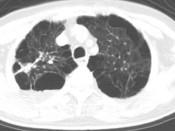

问题 男,76岁,气喘数年,胸痛1个月余,结合影像图像,选择最可能的诊断 ( )

选项 A.右上肺结核球 B.肺间质纤维化 C.右上肺瘢痕癌 D.右上肺错构瘤 E.右上肺肉瘤

答案 C